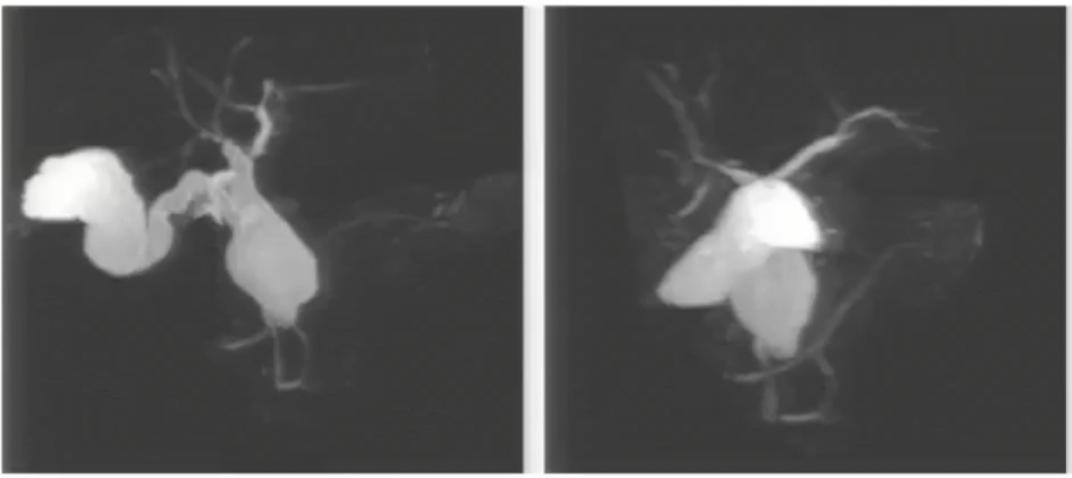

图1:腹膜后方下腔静脉处于腹主动脉左侧;左肾静脉出左肾门后,汇入下腔静脉路径缩短

下腔静脉畸形

下腔静脉畸形 以双下腔静脉畸形及左下腔静脉畸形最常见。

左下腔静脉畸形为肾下段下腔静脉在主动脉的左侧上升,与左肾静脉汇合,通过主动脉前方与右肾静脉汇合,并在此水平上形成正常的右下腔静脉。

双下腔静脉畸形表现为左下腔静脉终止于左肾静脉,通过主动脉前方汇入右下腔静脉。

临床意义:

绝大多数情况无症状,不具有临床意义; 先天性下腔静脉畸形是引起特发性深静脉血栓的高危因素之一; 对涉及心脏、肝脏、肾脏及腰膜后的手术,可能会增加手术风险。

案例分享:

图11:腹主动脉两侧均有下腔静脉影,左侧下腔静脉向上与左肾静脉汇合后,在腹主动脉前方绕行,移行为右侧下腔静脉